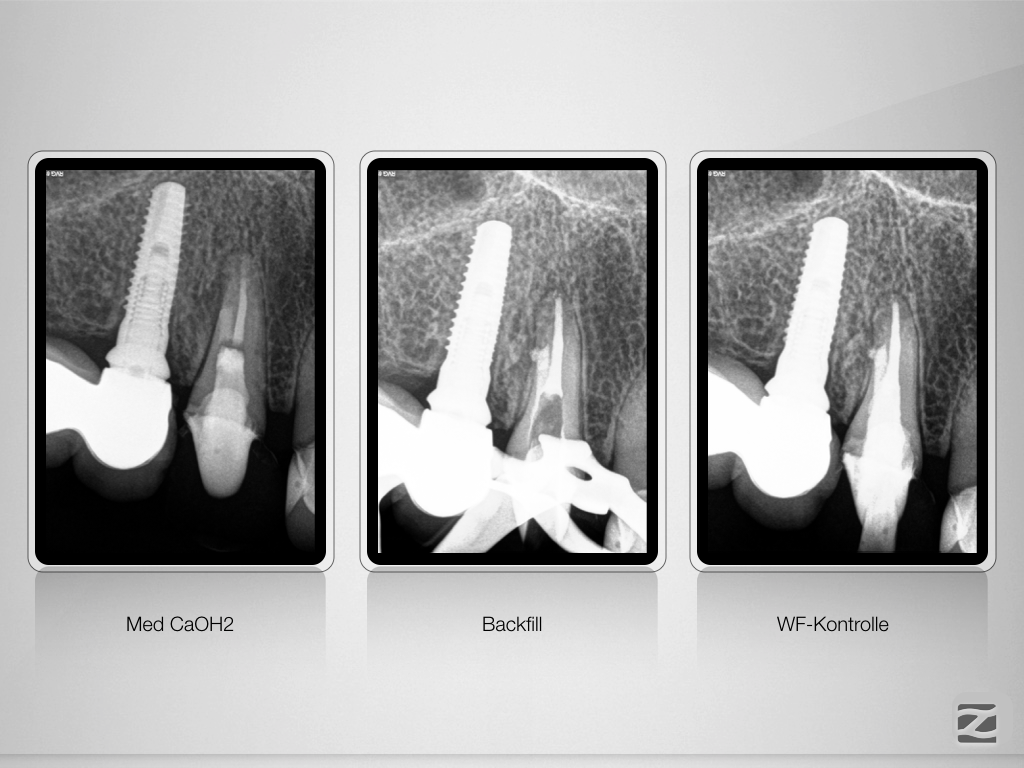

13D.014 Veröffentlicht 21. Januar 2020 am 1024 × 768 in Wer hat Angst vor’m bösen Stift? Teil 2, Zirkonoxidstift